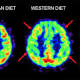

Mediterranean diet may protect against Alzheimer's

A Western-style diet triggers changes in the brain that may predispose patients to Alzheimer's disease decades before they show any sign of cognitive decline, according to new research by Weill Cornell Medicine investigators. In two studies, published ...